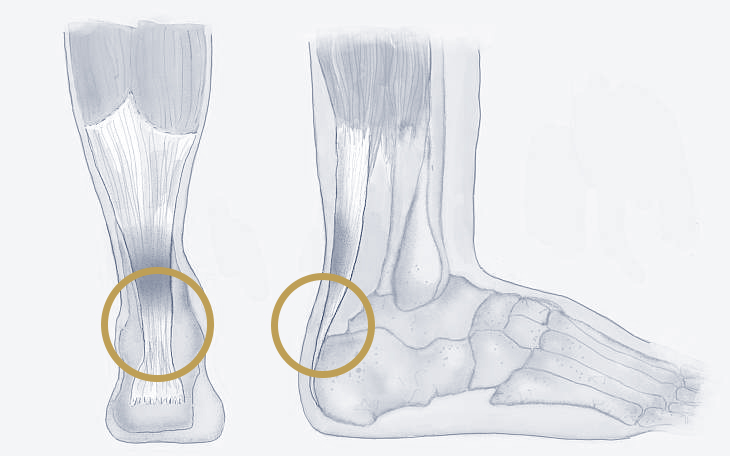

Bildquelle: www.docset.de

Symptome

Typisch sind Schmerzen, Schwellung, Bluterguss und eine eingeschränkte Beweglichkeit im Bereich des betroffenen Gelenks. Je nach Schweregrad des Risses kann das Gelenk instabil sein und das Gehen erschweren.

Ursachen

Bänderrisse entstehen meist durch ein Trauma, wie z.B. ein Umknicken des Fußes beim Sport oder im Alltag.

Konservative Therapie

Kühlung, Entlastung, Kompressionsverband, Hochlagern des Fußes, Schmerzmittel und Physiotherapie zur Kräftigung der Muskulatur und Verbesserung der Koordination können die Heilung fördern. In manchen Fällen ist eine Ruhigstellung im Gips oder einer Orthese erforderlich.

Operative Therapie

Bei schweren Bänderrissen, insbesondere wenn eine Instabilität des Gelenks besteht oder die konservative Therapie nicht ausreichend hilft, kann eine Operation in Erwägung gezogen werden. Dabei werden die gerissenen Bänder genäht oder durch ein Transplantat ersetzt.